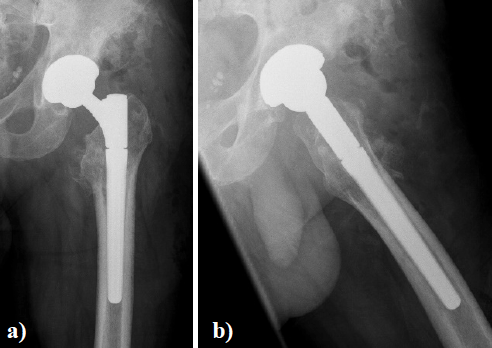

In August 2013 THA was performed due to a girdlestone situation after septic osteoarthritis of the hip (Figure 1) in a 46 year old male patient using a MRP Titan revision stem (Diameter: 18mm, length: 140 mm) (Peter Brehm GmbH, Weisendorf, Germany) and a cementless cup (Allofit - IT; Diameter 54 mm, Zimmer, Warsaw, USA) and a ceramic on ceramic bearing (head diameter: 36 mm) (Figure 2). The patient was 175 cm tall and weighed 105 kg (body mass index: 34.3 Kg/ m2). 2 weeks later revision surgery due to recurrent dislocation (Figure 3) was performed. Revision of the acetabular component was done using an Allofit - Classic- cup, Diameter 56 mm (Zimmer, Warsaw, USA)). The neck component was exchanged from small to medium size (Figure 4). A ceramic on PE bearing was implanted (head diameter: 32 mm). Postoperative healing was uneventful. The patient was out of any complaints. In February 2016 the patient started suffering from slight thigh pain but detected crepitation in the region of the left hip. X-ray of the left hip in 2 planes in May 2016 revealed an asymmetrically gap of the stem / neck junction (Figure 5). During revision surgery of the left hip breakage of the cone of the morse taper junction was visible (Figure 6). Removal of the well-fixed stem was performed via a distal fenestration. After fixation with cerclage wires a bended MRP Titan revision stem (Diameter: 19 mm, Length: 200mm with long neck and extension sleeve) was implanted using a 32 mm ceramic head (Figure 7). Postoperative healing was uneventful.

Figure 5. X - ray of the left hip in 2 planes: ap view a. and lateral; b. of the left hip reveals an asymmetrically gap of the stem / neck junction and radiolucent lines in zone 1,7,8, and 14 according to Gruen.